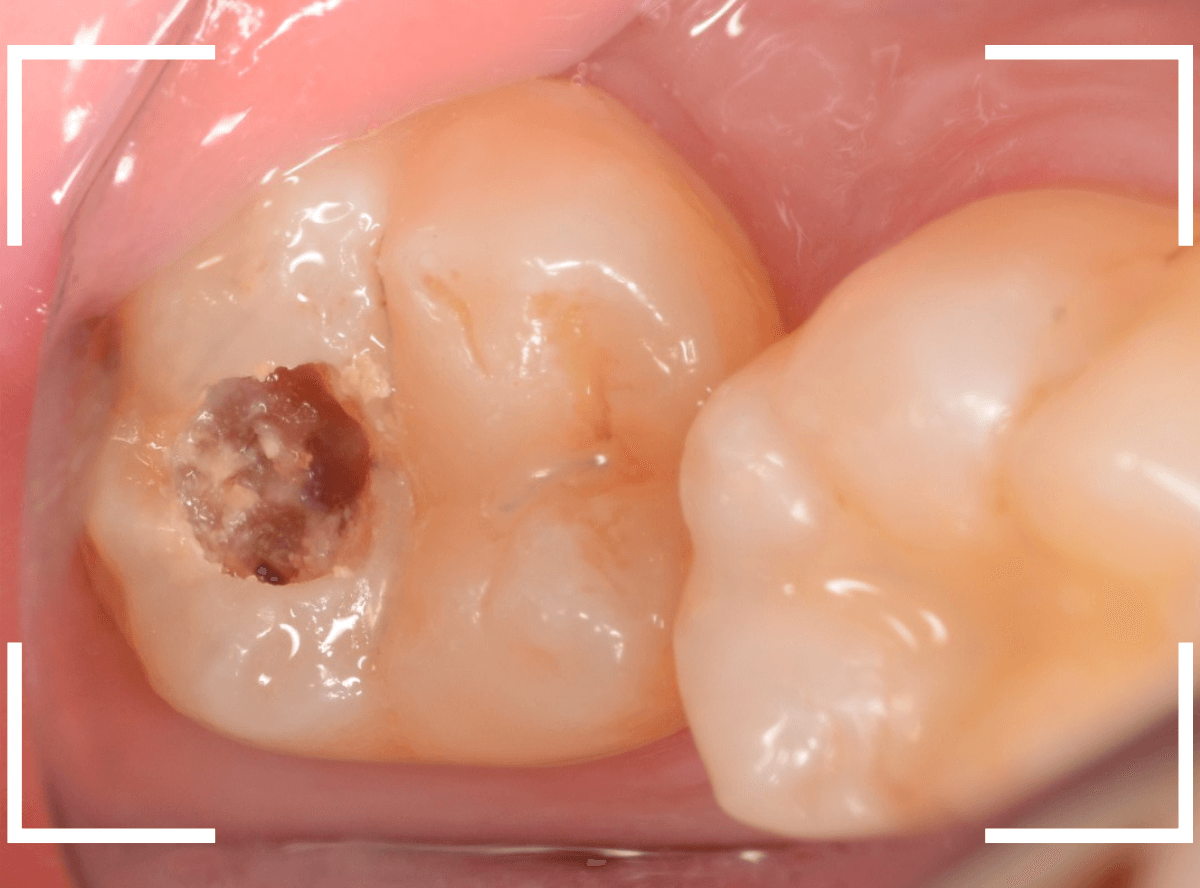

虫歯の治療希望で来院された患者さんです。

レジンが欠けて大きな穴が空いているのが見えます。

このような場合は、中で虫歯が進行している事が多いです。

(レジンの中で虫歯が進行してレジンに穴が空いた、レジンが欠けたのを放置して虫歯が進行したパターンなどがあります)